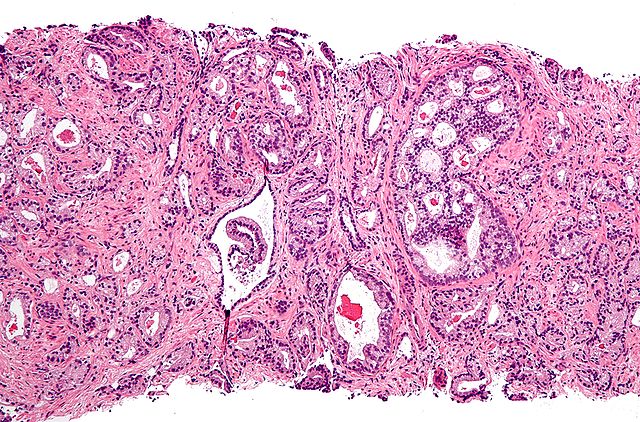

«Αν και σχεδόν όλοι οι άνδρες θα έχουν ιστολογικές ή μικροσκοπικές ενδείξεις καλοήθους υπερπλασίας του προστάτη μέχρι να μπουν στην όγδοη δεκαετία της ζωής τους, η κατάσταση δεν θα χρειασθεί θεραπεία πριν αρχίσει να προκαλεί συμπτώματα», διευκρινίζει ο πρόεδρος της Ελληνικής Εταιρείας Ουρολογικής δρ Ηρακλής Πούλιας, τ. διευθυντής στην Ουρολογική Κλινική του Κοργιαλένειου Μπενάκειου Νοσοκομείου ΕΕΣ.